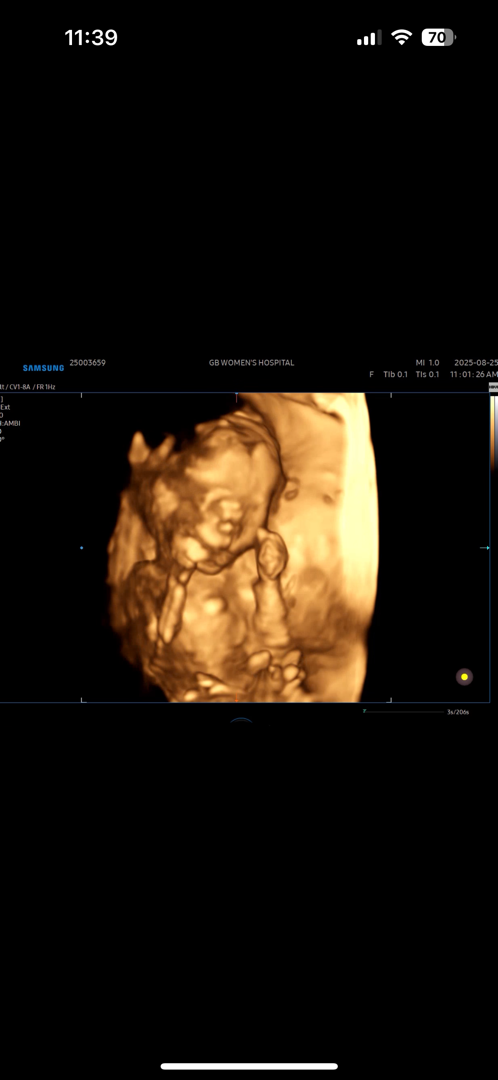

8/25일 18주 3일차고 9/24일 정밀 초음파 앞두고 있는데 ㅠㅠ 입술위에 진한선이 보이는것 같아서 정밀 초음파 너무 떨리고 그렇네요 ㅠㅠ 혹시 아기초음파사진에 저같은분 있나요 1.2차 저위험군 이상소견 없었고 초음파 볼때도 잘자라고 있다고 이상소견 없으셨는데 집와서 영상을 다시보니 ㅠㅠ 진한선이 보이는것 같아 불안하고 걱정되서요

각도에따라서 달라요!!!! 저도 처음에 입술위에 줄이있었는데 각도를 다르게해서보여주시니까 없더라구요~ 아무문제없데요~